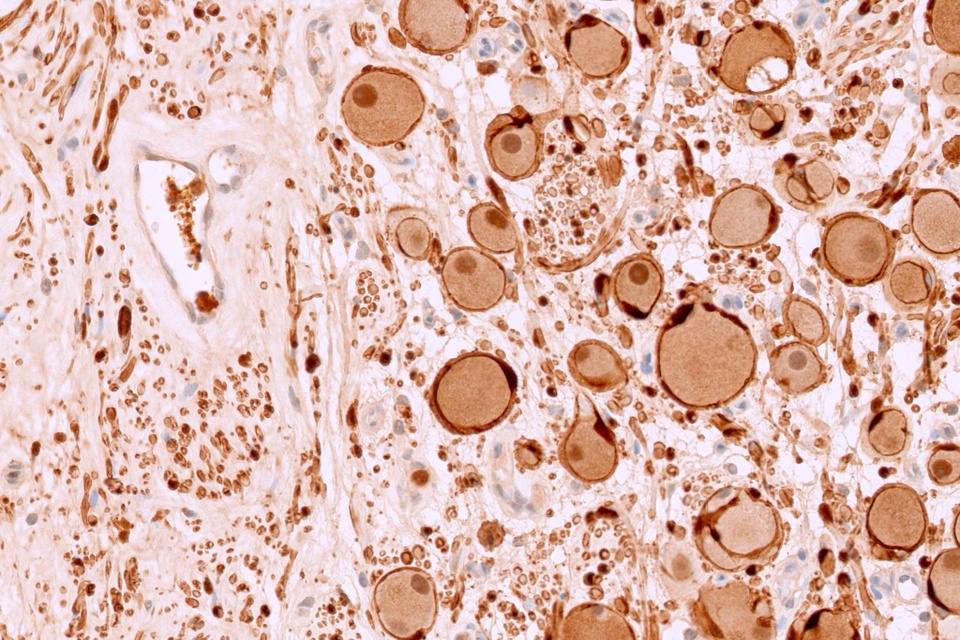

Mẫu mô của bệnh nhi khi được quan sát dưới kính hiển vi. Ảnh: BVCC.

Kết quả xét nghiệm xác định khối u là u nguyên bào thần kinh đệm típ đang biệt hóa (Ganglioneuroblastoma) - một dạng u thần kinh hiếm gặp ở trẻ em. Căn bệnh này nếu không được phát hiện kịp thời có thể dẫn tới di căn, gây khó khăn trong điều trị và ảnh hưởng lớn đến khả năng sống của người bệnh.

Theo bác sĩ chuyên khoa I Phạm Thị Hoa, khoa Giải phẫu bệnh, Bệnh viện Việt Nam - Thụy Điển Uông Bí, ganglioneuroblastoma là khối u hình thành từ các tế bào thần kinh chưa trưởng thành, thường xuất hiện dọc theo cột sống, trong ổ bụng, ngực hoặc tuyến thượng thận.